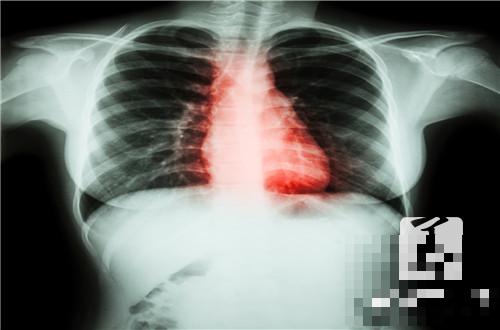

心脏预激综合症是指房室传导过程中所存在的异常病变,主要会存在提早兴奋心室的症状表现,通常在涉及到病变期间,其特征是会出现心律失常的异常表现,如果未能及时对于心脏部位所存在的失常有效护理,是会造成心脏压力性的日益增加。